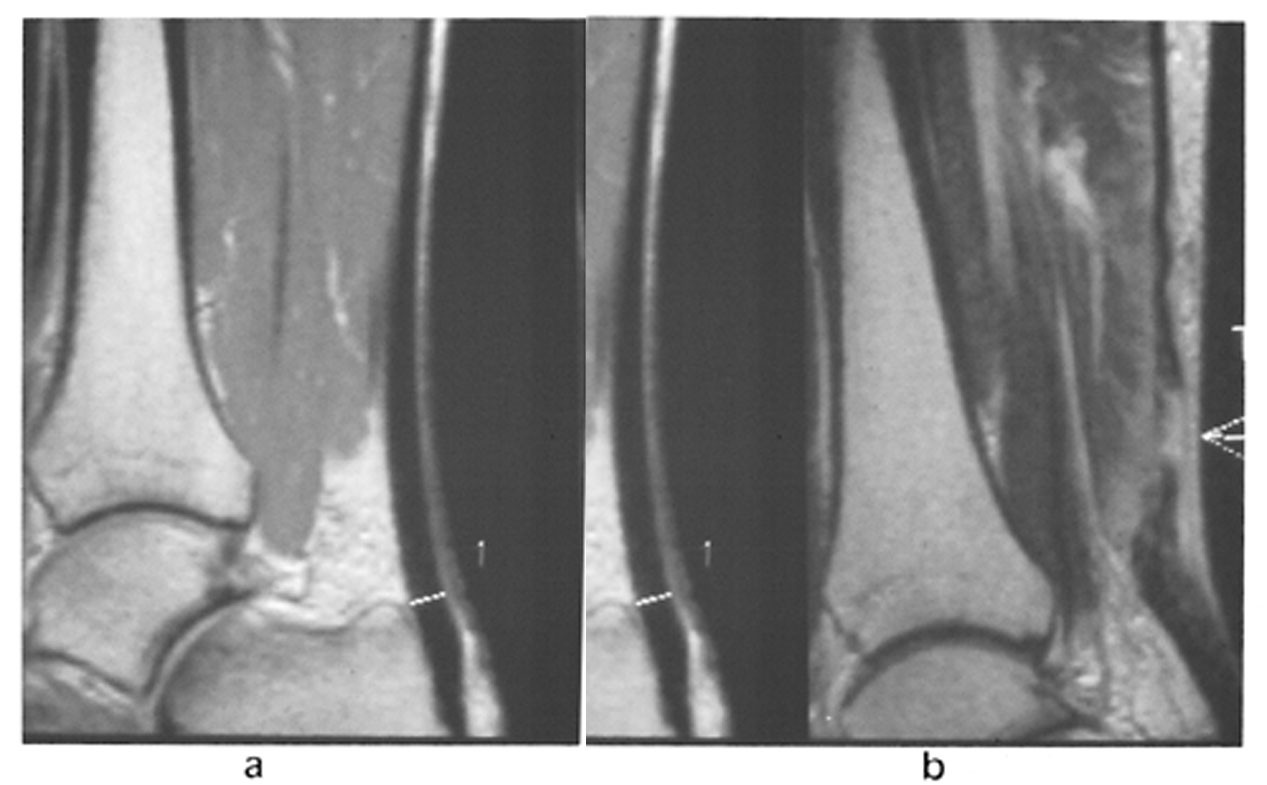

MR er velegnet til å diagnostisere patologiske forhold i akillessenen (fig 17), intraartikulære og periartikulære ankelleddsstrukturer og sinus tarsi-syndrom. En stabil osteochondritis dissecans i os talus kan være ledsaget av margødem i tilslutning til osteokondrittsengen. Margødemet kan forklare smertene. Sinus tarsi-syndrom kan diagnostiseres hvis det er for lite eller for mye væske i sinus tarsi (13). Funnet kan forklare bakfotsmerter hvor man ellers ikke finner andre forklaringer. Stressfrakturer gir nedsatt signal på T1-vektet sekvens og økt signal på STIR-sekvens.

Akutt muskelskade kan være forårsaket enten av direkte penetrerende kraft, som gir en laserasjon, eller av stump kraft, som gir kontusjon (fig 18). Det er sjelden pasienter med laserasjon kommer til MR i den akutte fase. Eventuell senkomplikasjon med fettdegenerasjon kan identifiseres som nedsatt muskelmasse og høysignal på T1-vektet sekvens. Ved muskelkontusjoner vil ofte T1-vektet sekvens være normal, mens STIR-sekvensen viser økt signal i muskelen.

Lange og trettende muskeløvelser kan gi et klinisk bilde med muskelsmerte, udefinerbar sårhetsfølelse, hevelse og stive ledd i timer og dager etterpå. Dette er kjent som DOMS (delayed onset muscle soreness) i engelsk litteratur. Det kliniske bildet kan vare opptil en uke. MR-funnet likner forandringene man ser ved mild grad av muskelkontusjon og kan være positivt i flere måneder (fig 19). Ved gjentatte øvelser kan man se forandringer ved muskel-sene-overgangen, forenlig med såkalt kronisk muskeloverforbrukssyndrom.